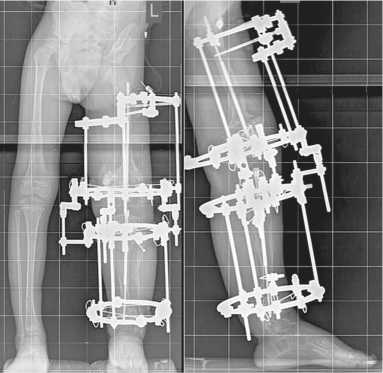

Из того же парапателлярного доступа производилось антеградное введение спицы-гида под рентгеновским контролем со входом через межмыщелковую зону по костно-мозговому каналу до уровня деформации в верхней трети большеберцовой кости. Остеотомия на вершине деформации выполнялась из доступа 1 см. Дополнительно в нижней трети голени через разрез кожи до 1 см выполнена остеотомия малоберцовой кости. Далее по спице-гиду производили рассверливание канала канюлированным сверлом диаметром 5,8 мм до дистального метафиза, введение внутренней части телескопического стержня до уровня непосредственно над дистальной зоной роста. Далее следовало введение соответственно укороченной внешней части диаметром 5,5 мм с вкручиванием резьбовой части канюлированной отверткой в проксимальный эпифиз большеберцовой кости, не заходя за линию зоны роста. Заключительным этапом размещения телескопического стержня большеберцовой кости было вкручивание резьбовой части в дистальный эпифиз таким образом, чтобы вся резьба оказалась дистальнее линии зоны роста. Скусывание выступающего отдела внутренней части выполняли непосредственно перед промыванием и послойным ушиванием парапателлярного доступа. Рентгеновский контроль целой конечности подтвердил корректное расположение телескопических стержней (рис. 2).

Спице-стержневого аппарат внешней фиксации, состоял из 2 кольцевых опор на голени, и кольцевой опоры в нижней трети бедра и сегментарной короткой дуги в верхней трети сегмента. В дистальной кольцевой опоре бедра и дистальной кольцевой опоре голени применяли лишь спицы диаметром 1,8 мм, проведенные на метафизарном уровне. В проксимальной дуге бедра применяли только стержни-шурупы диаметром 4,5 мм, введенные в проксимальный метафиз, а в проксимальной опоре голени — комбинация спиц и стержня-шурупа, расположенных также на метафизарном уровне (рис. 3). На уровне коленного сустава для соединения опор применяли шарнирные узлы.

Рис. 2. Рентгенограмма, выполненная в процессе оперативного вмешательства на этапе после остеотомий, установки интромедуллярных стержней и до наложения аппарата внешней фиксации

Рис. 3. Рентгенограммы, выполненные после завершения комбинированного остеосинтеза